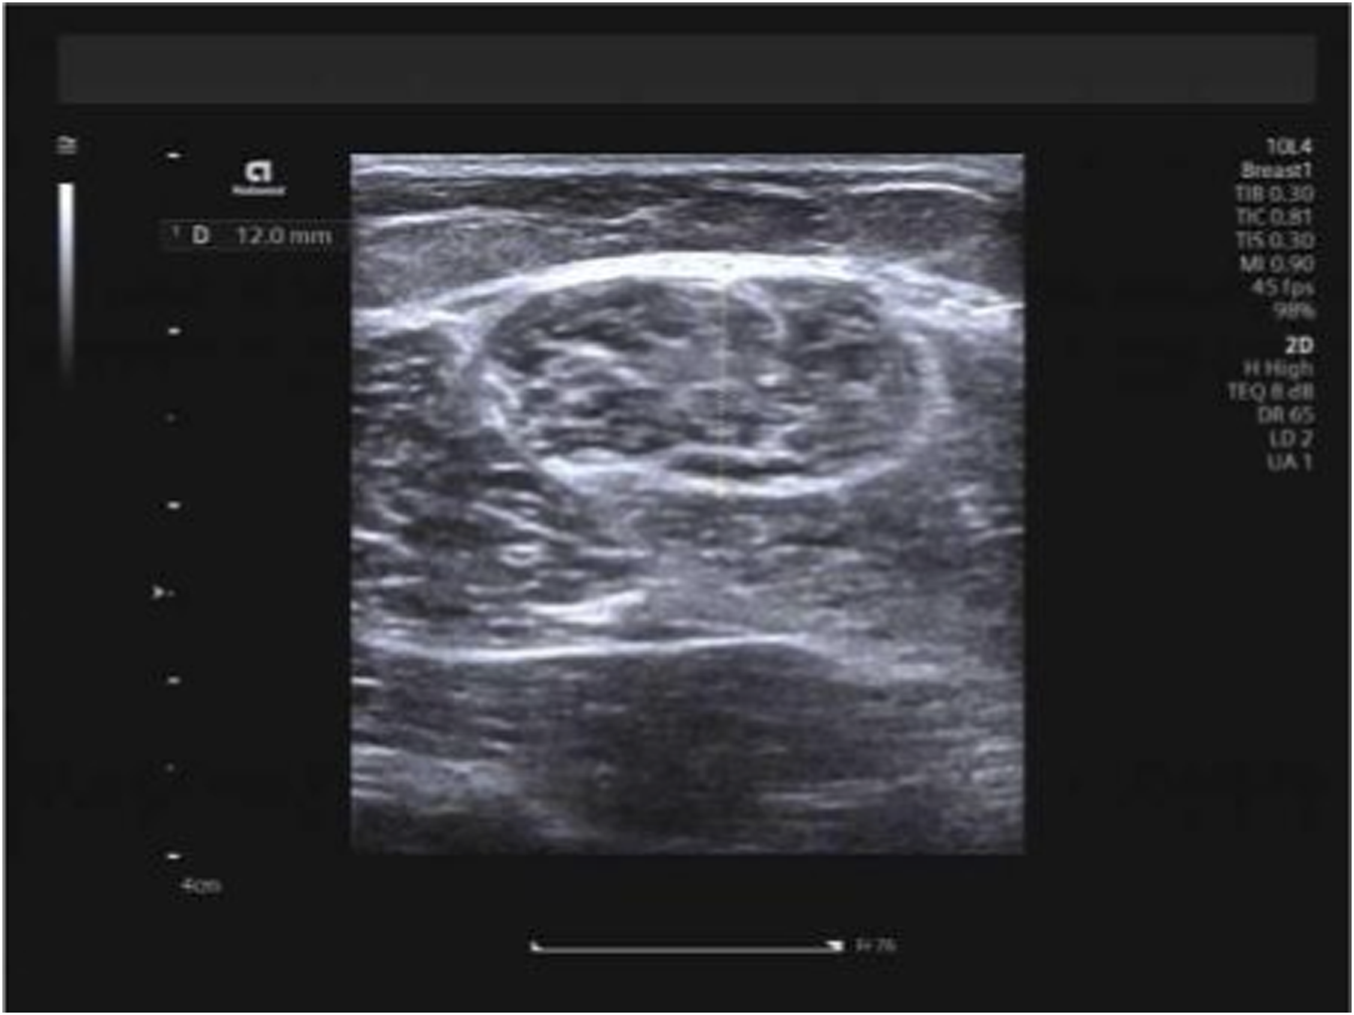

Hamstring muscles (specifically the long head of the biceps femoris and semitendinosus) were examined with participants in the prone position, legs extended naturally and body fully relaxed. The measurement site was standardized as the mid-belly region of each muscle, located approximately 15 cm distal to the ischial tuberosity along the longitudinal axis of the muscle fibers. Muscle thickness was measured on B-mode ultrasound images as the vertical distance between the superficial and deep fascia at this site, with the transducer placed transversely to the muscle fibers. Three consecutive measurements were taken and averaged to obtain the final value (Figures 2, 3). Hamstring measurements were obtained in two positions: the neutral position and the 90° knee-flexed position. During measurements performed at 90° knee flexion, the angle was maintained using a custom foam pad positioned beneath the lower leg to support the shank, ensuring a consistent 90° angle between the femur and tibia. The participant’s position was monitored throughout image acquisition to prevent unintended movement or muscle activation. In this study, measurement posture refers to the specific body position adopted during imaging (e.g., neutral, flexed, or extended), and measurement technique refers to the probe orientation or imaging plane (transverse or longitudinal) used during shear-wave elastography. Importantly, for all examined muscles—including the upper trapezius, biceps femoris long head, and semitendinosus—SWE measurements were performed in both longitudinal and transverse planes at the same anatomical locations. To ensure methodological consistency, the acquisition depth was standardized for each muscle group: 0.5–1.0 cm for the upper trapezius and 1.0–2.0 cm for the hamstring muscles (long head of the biceps femoris and semitendinosus), with minor adjustments made only to ensure that the ROI was positioned at the center of the muscle belly. A fixed 1.0 × 1.0 cm circular region of interest (ROI) was applied uniformly across all measurements. This dual-orientation approach was intentionally implemented to evaluate the consistency and direction-dependent characteristics of muscle stiffness, in accordance with previous recommendations.

FIGURE 3

Measurement of semitendinosus thickness.